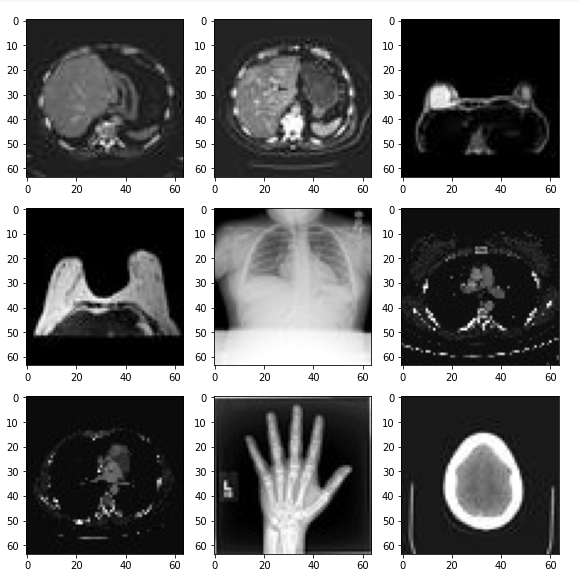

MedNISTDataset

受 Medical Segmentation Decathlon(医学分割十项全能)的启发,上海交通大学的研究人员创建了医疗图像数据集 MedMNIST,共包含 10 个预处理开放医疗图像数据集(其数据来自多个不同的数据源,并经过预处理)。和 MNIST 数据集一样,MedMNIST 数据集在轻量级 28 × 28 图像上执行分类任务,所含任务覆盖主要的医疗图像模态和多样化的数据规模,作为 AutoML 在医疗图像分类领域的基准。